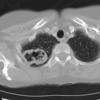

Case 14 RLL pneum CT

Date: 04/17/2005

Views: 5646